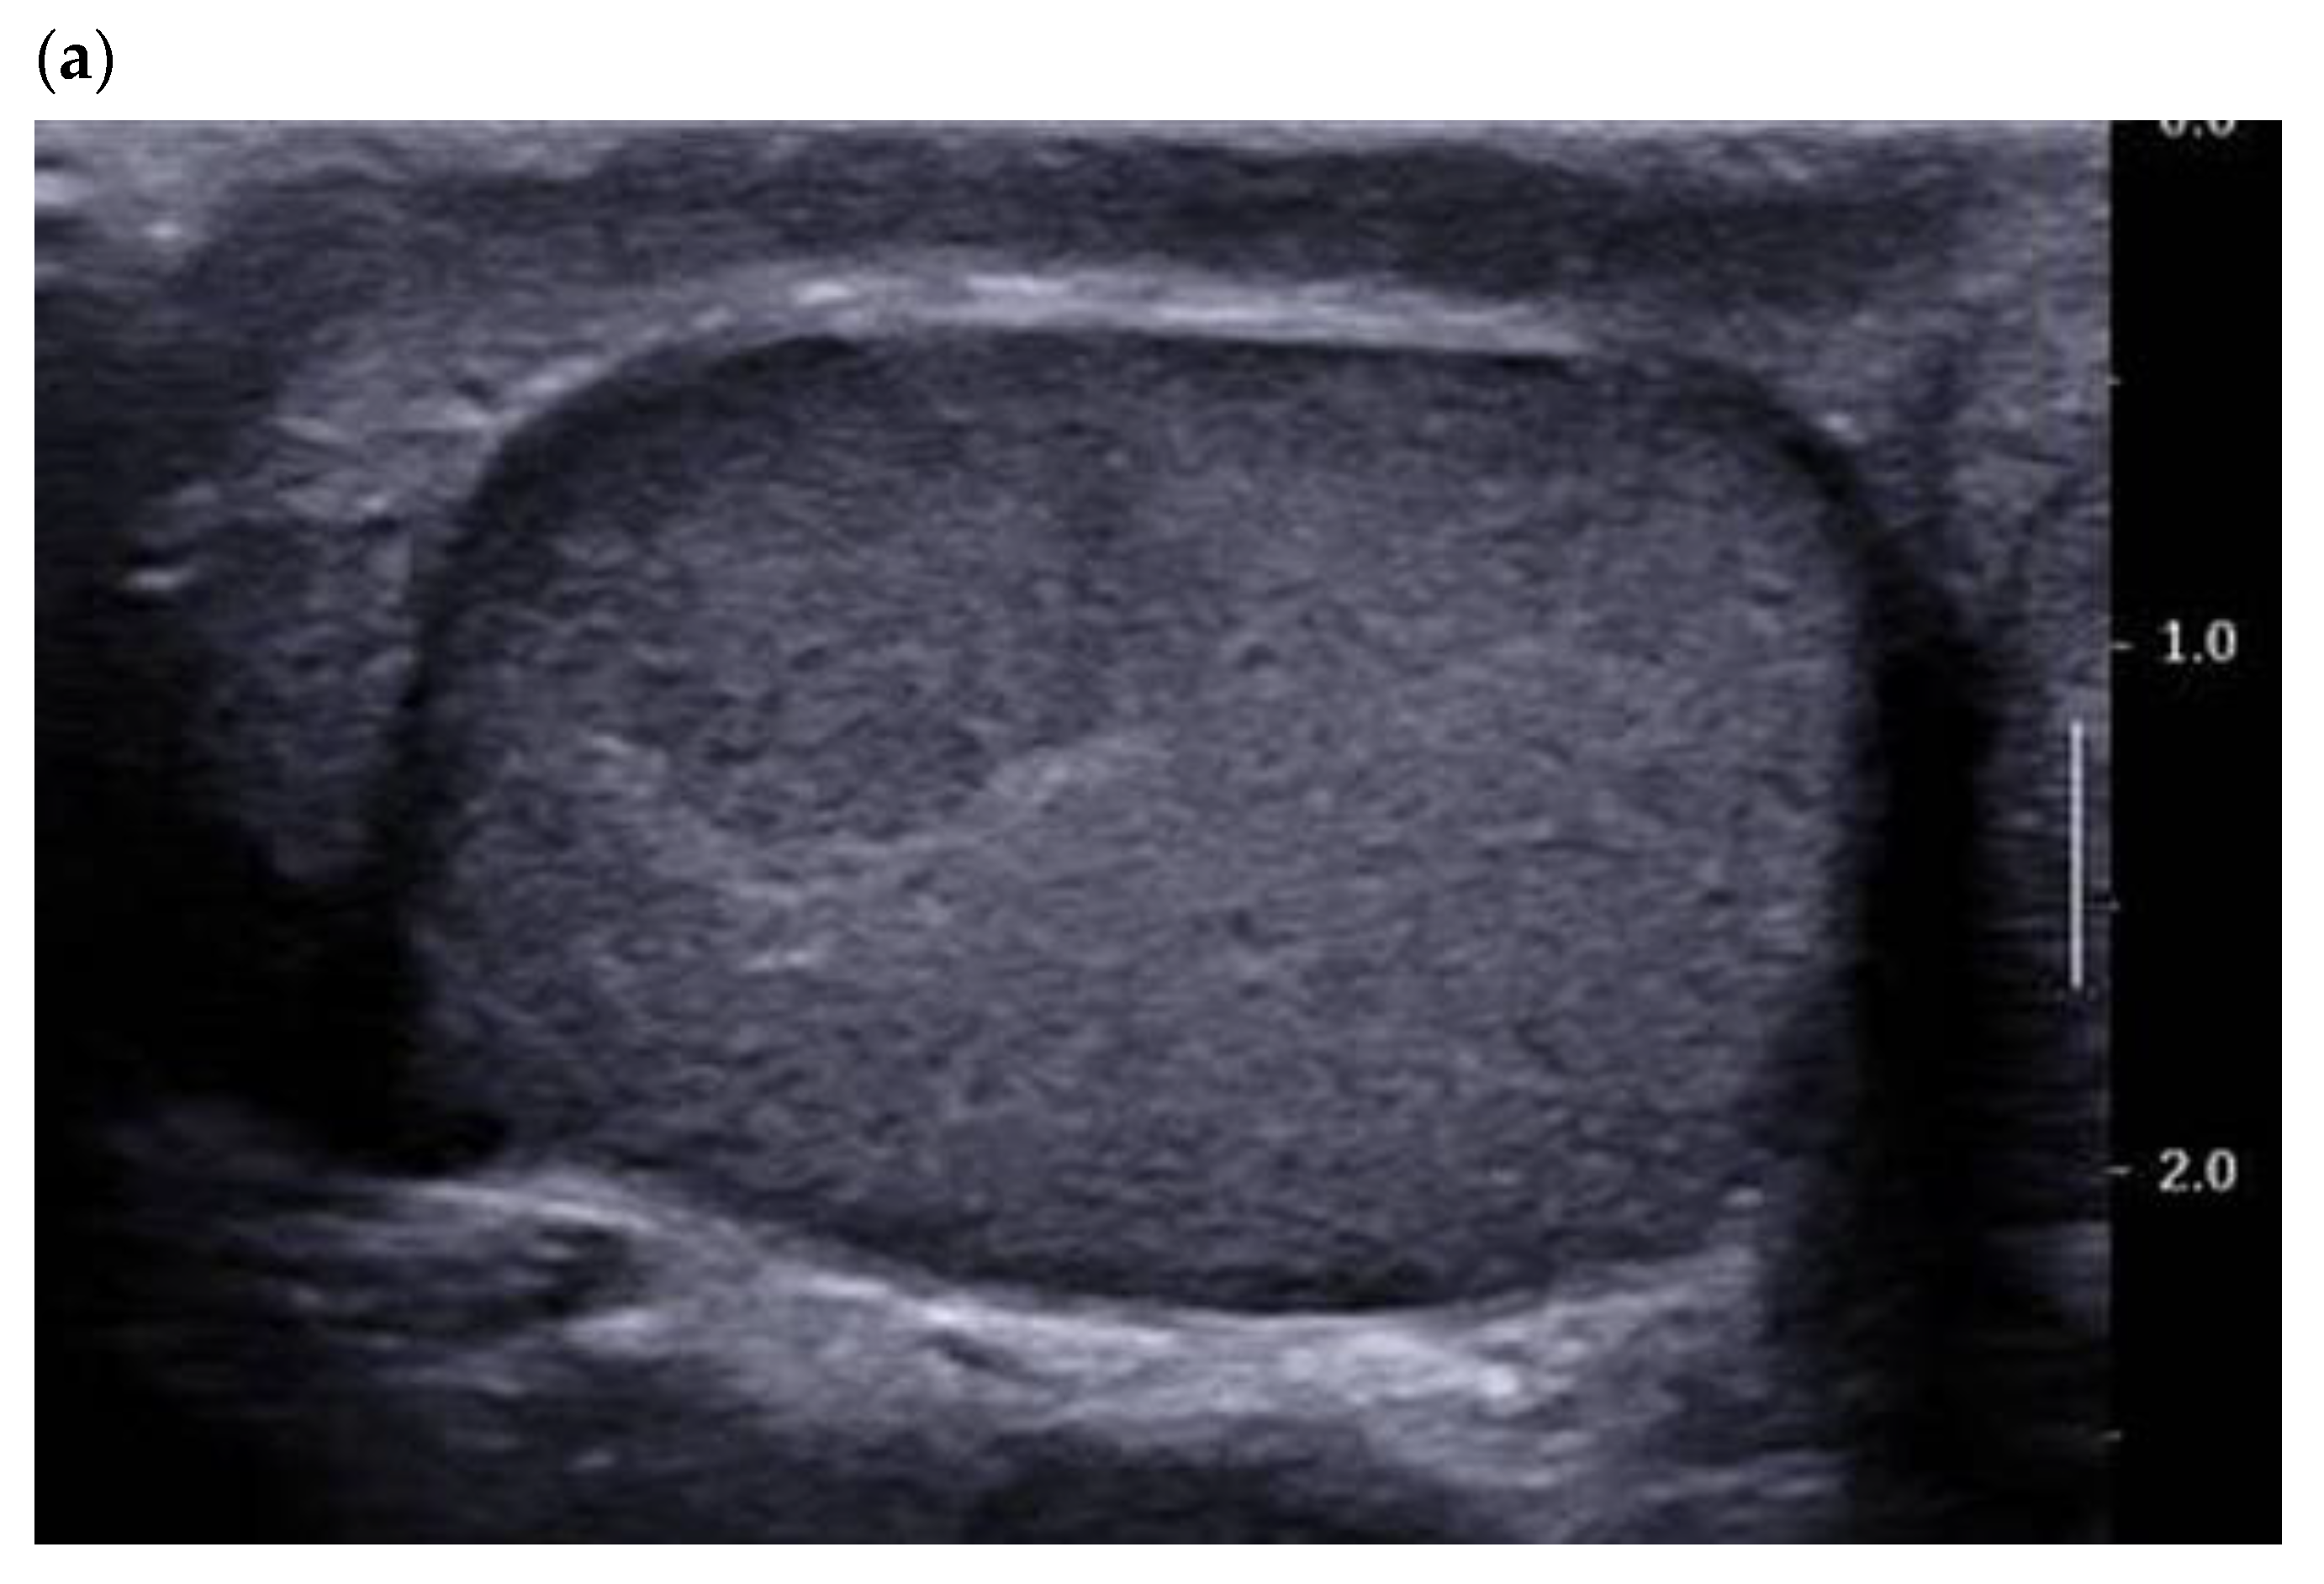

Figure 1.

28-year-old patient presenting with left testicular pain (significant left varicocele during the exam). Typical LCT 12 × 9 mm on B mode us (a) and color Doppler (b) discovered on the right testis. Well-defined lobulated solid lesion moderately hypoechoic and homogeneous echo structure with normal adjacent pulp and absence of microlithiasis. The lesion is hyper vascularized with a mixed peripheral and internal pattern. (c) From left to right: Macroscopic view of the patient’s LCT after enucleation. The typical “golden brown” color of the lesion often allows the surgeon and the pathologist to confirm the diagnosis during surgery. HE × 30 Hematein–Eosin coloration showing a high cellular density with no necrosis. HE × 40 with an endothelial cell marker anti CD-31, showing a rich vascularization of the tumor. Courtesy of Pr S. Ferlicot, Department of Anatomo-pathology, Bicêtre Hospital.

Color Doppler allows for qualitative assessment of tumor vasculature and its organization. Most recent ultrasound devices have a Doppler module optimized for the detection of the microflow associated with a decrease in motion artifacts (SMI® from Canon or Angioplus RT® from Aixplorer). Maxwell et al. found that close to 95% of lesions were hypervascular compared with the adjacent pulp, with an enveloping vascularization pattern or a mixed (central and peripheral) pattern of the vascular architecture [10]. These results corroborate the literature data [12] and the most recent case reports [15]. The presence of internal vascularization is more controversial in the literature, since it ranges from 0% in Maizlin et al. in 2014 to close to 45% in Maxwell et al. in 2016 (Figure 1) [10,12].

These differences can be explained by improvements in the sensitivity of ultrasound probes and in the performance of the Doppler mode. The use of ultrasensitive Doppler further improves the detection of intra- and peri-lesional flows and ameliorates identification of the enveloping pattern, which is suggestive of LCTs (Figure 2) [16].